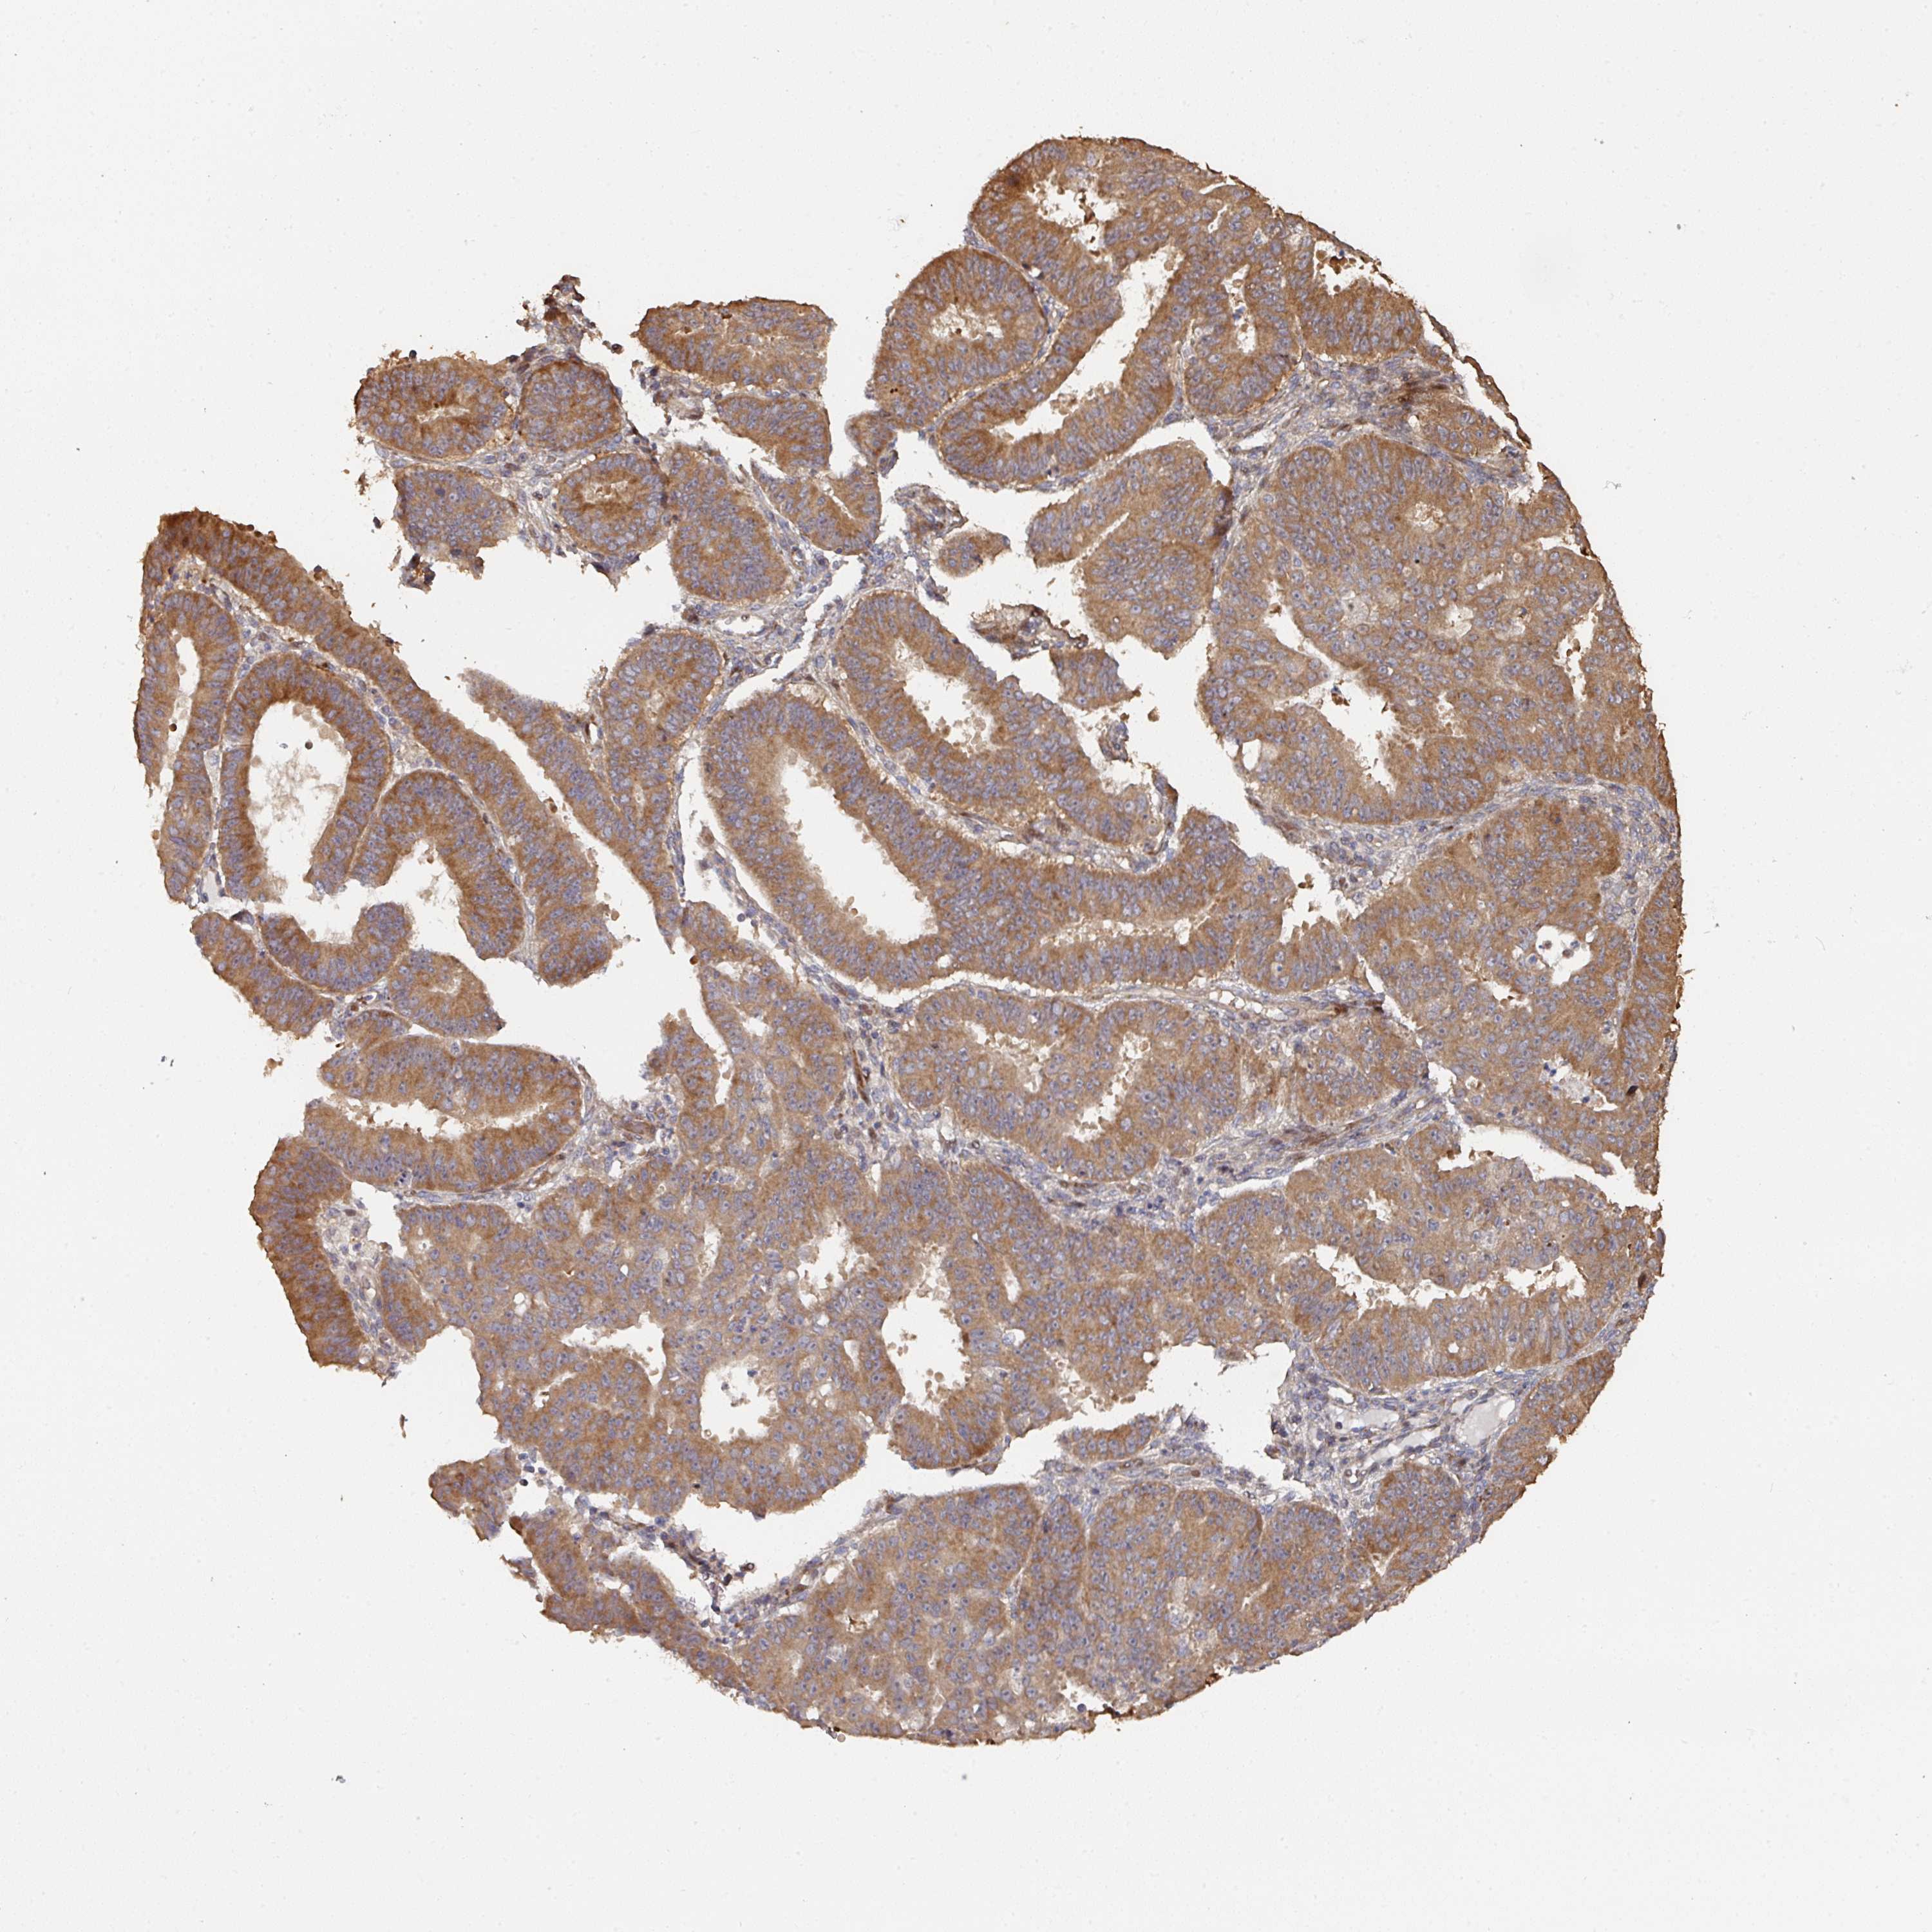

OVARIAN CANCER - Protein expressioni

A mouse-over function shows sample information and annotation data. Click on an image to view it in a full screen mode. Samples can be filtered based on level of antibody staining by selecting one or several of the following categories: high, medium, low and not detected. The assay and annotation is described here.

Note that samples used for immunohistochemistry by the Human Protein Atlas do not correspond to samples in the TCGA dataset.

Antibody stainingi

Antibody staining in the annotated cell types in the current human tissue is reported as not detected, low, medium, or high, based on conventional immunohistochemistry profiling in selected tissues. This score is based on the combination of the staining intensity and fraction of stained cells.

Each image is clickable and will lead to virtual microscopy that enables deeper exploration of all samples and also displays staining intensity scores, fraction scores and subcellular localization as well as patient and tissue information for each sample.

Antibody HPA047237

Staining

High

Medium

Low

Not detected

Intensity

Strong

Moderate

Weak

Negative

Quantity

>75%

75%-25%

<25%

None

Location

Nuclear

Cytoplasmic/membranous

Cytoplasmic/membranous,nuclear

Cystadenocarcinoma, serous, NOS

Carcinoma, endometroid

Cystadenocarcinoma, mucinous, NOS

Carcinoma, NOS